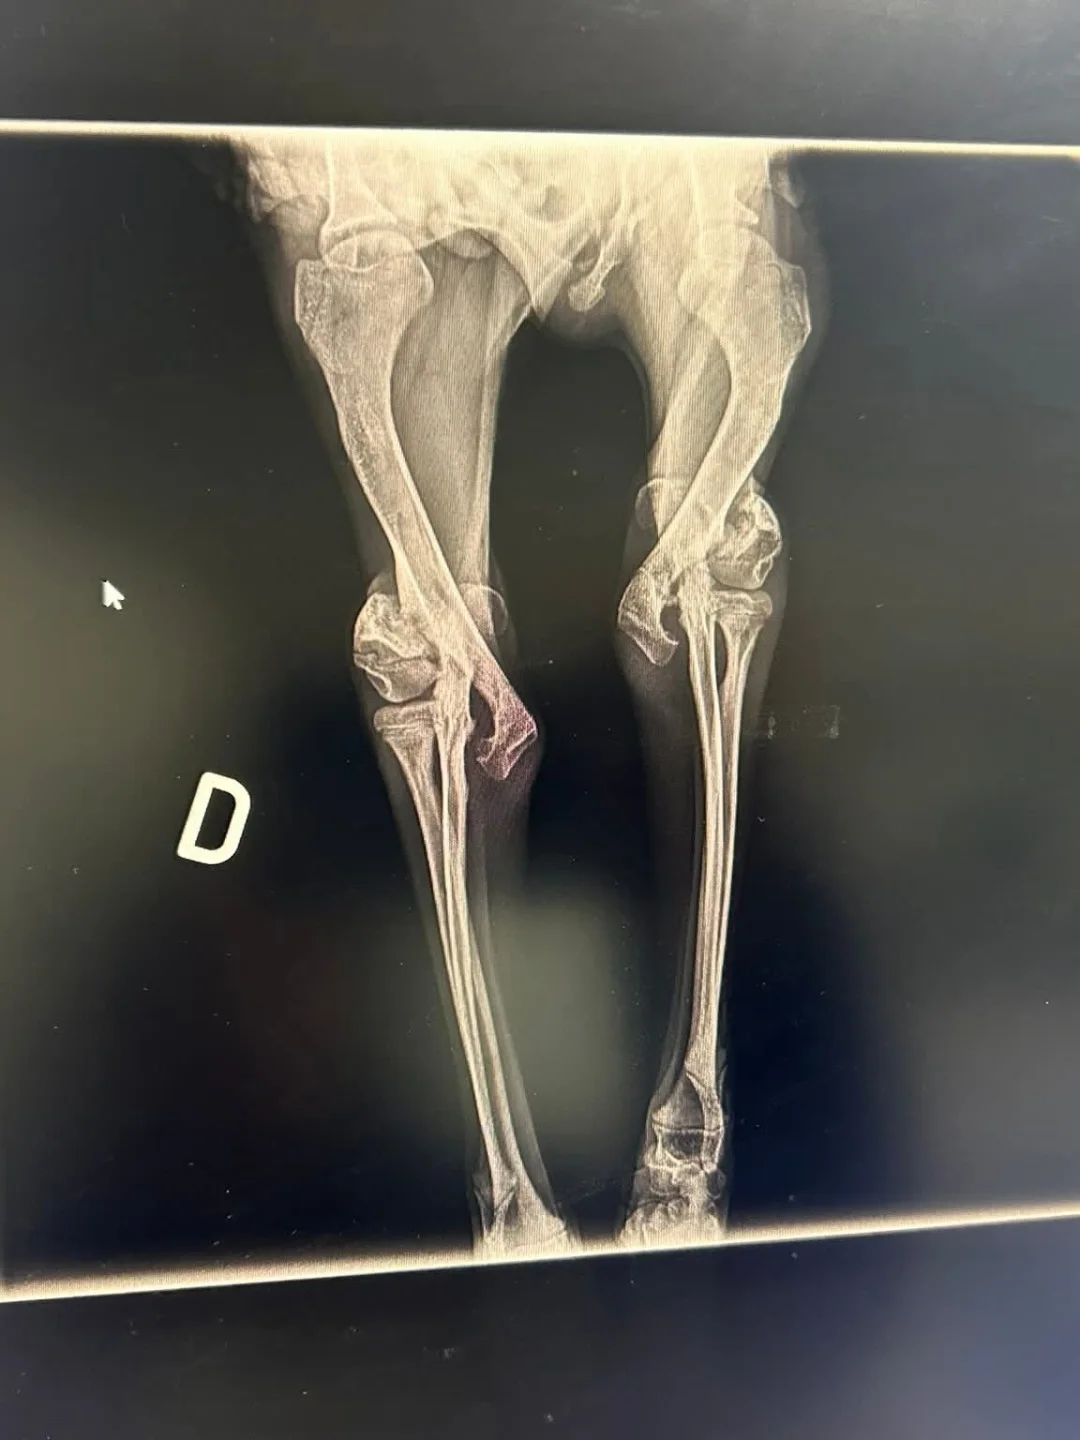

Estamos luchando por recuperar sus codos porque con sus cuatro meses de vida ya los tiene rotos.

La cirugía fue el lunes pasado y se complicó bastante porque sus huesitos no resisten las agujas y fue casi imposible colocárselos.

Ahora está inmovilizado con férula de escayola y sin poder apoyar nada de nada, con lo que tiene que estar en una cuna de viaje durante un mes por lo menos.